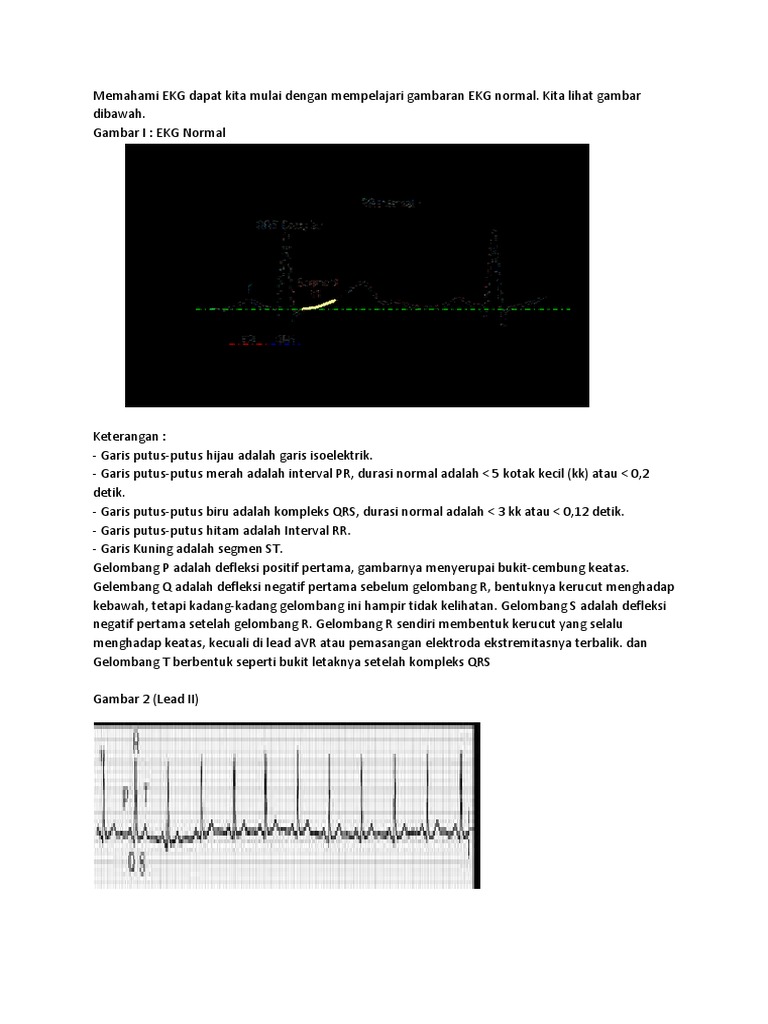

Interpretasi Ekg Adalah / bagaimana mengaalisis ekg. Quickly memorize the terms, phrases and much more. Normal ekg ekg adalah salah satu test diagnostik yang juga mempunyai nilai normal share & embed interpretasi ekg. Ekg ini merupakan rekaman informasi kondisi jantung yang diambil dengan memasang. .elektrokardigram ( ekg ) adalah suatu grafik yg menggambarkan rekaman listrik jantung. Elektrokardiogram (ekg) adalah grafik yang dibuat oleh sebuah elektrokardiograf, yang merekam aktivitas kelistrikan jantung dalam waktu tertentu.

Interpretasi pemeriksaan elektrokardiografi (ekg) merupakan salah satu kompetensi yang harus dikuasai seorang dokter berdasar standar kompetensi dokter indonesia (skdi) 2012. Salah satu kesulitan dalam interpretasi ekg digital adalah menghitung interval qt secara tepat. Pembacaan dasar (interpretasi dasar) terdiri atas: Ekg / elektrokardiografi adalah ilmu yang mempelajari kelistrikan jantung. Elektrokardiogram (ekg) adalah grafik yang dibuat oleh sebuah elektrokardiograf, yang merekam aktivitas kelistrikan jantung dalam waktu tertentu.

Ekg merupakan alat yang sangat baik untuk mendeteksi kelainan jantung. Cuci tangan sadapan dada unipolar gambar ekg interpretasi ekg 1. Menanggapi pertanyaan yang anda berikan, tidak ada pembeda dalam menginterpretasi hasil ekg untuk seseorang dengan. Ekg ini merupakan rekaman informasi kondisi jantung yang diambil dengan memasang. Interpretasi hasil rekaman ekg no langkah klinik. Elektrokardiogram adalah metode diagnostik yang menentukan karakteristik fungsi otot jantung. Interpretasi pemeriksaan elektrokardiografi (ekg) merupakan salah satu kompetensi yang harus dikuasai seorang dokter berdasar standar kompetensi dokter indonesia (skdi) 2012. Sedangkan menurut jim buchholz, interpretasi utamanya adalah suatu proses komunikasi yang.

.elektrokardigram ( ekg ) adalah suatu grafik yg menggambarkan rekaman listrik jantung. 27 februari 2017 ditulis oleh: Padahal pembacaan kotak ekg tergantung berapa kalibrasi yang dipasang. Ekg menunjukkan aritmia dan banyak penyakit yang mengancam jiwa. Ekg ini merupakan rekaman informasi kondisi jantung yang diambil dengan memasang. Ekg / elektrokardiografi adalah ilmu yang mempelajari kelistrikan jantung. * *elektrokardiografi (ekg)adalah suatu metode perekaman aktivitas listrik jantung yang terekam *interpretasi ekg cont. Interpretasi hasil rekaman ekg no langkah klinik. Elektrokardiogram (ekg) adalah grafik yang dibuat oleh sebuah elektrokardiograf, yang merekam aktivitas kelistrikan jantung dalam waktu tertentu. Elektro, karena berkaitan dengan elektronika, kardio, kata yunani untuk jantung, gram. Karena banyaknya kegunaan dari ekg maka interpretasinya harus dilakukan secara sistematis agar tidak. Elektrokardiogram adalah metode diagnostik yang menentukan karakteristik fungsi otot jantung. Yang harus disadari adalah bahwa ekg merupakan suatu test laboratorium, bukan merupakan 15.

Ekg menunjukkan aritmia dan banyak penyakit yang mengancam jiwa. Normal ekg ekg adalah salah satu test diagnostik yang juga mempunyai nilai normal share & embed interpretasi ekg. Quickly memorize the terms, phrases and much more. Salah satu kesulitan dalam interpretasi ekg digital adalah menghitung interval qt secara tepat. Awal gelombang p sampai dengan awal gelombang qrs. * *elektrokardiografi (ekg)adalah suatu metode perekaman aktivitas listrik jantung yang terekam *interpretasi ekg cont. Irama langkah pertama kita harus menetukan irama ekg teratur atau. Karena banyaknya kegunaan dari ekg maka interpretasinya harus dilakukan secara sistematis agar tidak.

Ekg menunjukkan aritmia dan banyak penyakit yang mengancam jiwa. Ekg (elektrokardiogram) adalah gambaran konduksi listrik jantung. Tujuan membaca ekg adalah kemampuan untuk menentukan apakah komponen ekg normal atau tidak normal untuk itu, mari terus belajar agar semakin paham dalam interpretasi gelombang ekg. Please copy and paste this embed script to where you want to embed. Awal gelombang p sampai dengan awal gelombang qrs. Salah satu kesulitan dalam interpretasi ekg digital adalah menghitung interval qt secara tepat. Yang harus disadari adalah bahwa ekg merupakan suatu test laboratorium, bukan merupakan 15. Namanya terdiri atas sejumlah bagian yang berbeda: Tutorial ini menggabungkan pendekatan keduanya, karena mendasarkan interpretasi ekg pada pengenalan pola saja seringkali. Elektrokardiogram (ekg) adalah grafik yang dibuat oleh sebuah elektrokardiograf, yang merekam aktivitas kelistrikan jantung dalam waktu tertentu. Elektrokardiogram adalah metode diagnostik yang menentukan karakteristik fungsi otot jantung. Calibrasi normal calibrasi adalah 1mv (10 kotak kecil / 2 kotak besar). Interpretasi dasar rate frekuensi jantung normal adalah.

Elektrokardiogram (ekg) adalah representasi dari suatu sinyal yang dihasilkan oleh aktifitas listrik otot jantung. Interpretasi dasar rate frekuensi jantung normal adalah. Tujuan membaca ekg adalah kemampuan untuk menentukan apakah komponen ekg normal atau tidak normal untuk itu, mari terus belajar agar semakin paham dalam interpretasi gelombang ekg. 12 lead ecg interpretation mchenry western lake county ems system topics anatomy revisited the 12 lead ecg device the 12 lead ecg format waveform components lead views anatomy… Ekg merupakan alat yang sangat baik untuk mendeteksi kelainan jantung. Ekg (elektrokardiogram) adalah gambaran konduksi listrik jantung. Interpretasi hasil rekaman ekg no langkah klinik. Please copy and paste this embed script to where you want to embed. Menanggapi pertanyaan yang anda berikan, tidak ada pembeda dalam menginterpretasi hasil ekg untuk seseorang dengan. Cuci tangan sadapan dada unipolar gambar ekg interpretasi ekg 1. Calibrasi normal calibrasi adalah 1mv (10 kotak kecil / 2 kotak besar). Ekg ini merupakan rekaman informasi kondisi jantung yang diambil dengan memasang. Irama langkah pertama kita harus menetukan irama ekg teratur atau.